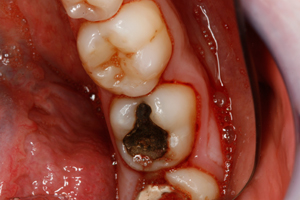

Thank you to our patients that have allowed us to show examples of our work

Have a look at just some of the many patient examples we have captured from BEFORE and AFTER their treatments and cosmetic surgeries.

From Whitening to Veneers, Fillings to Cosmetic Teeth Makeovers, here are some examples of the work that Dr. Dadabhai has provided to his patients to give them a more confident smile and a positive, pain free feeling.

Slide your computer mouse or finger (touch screens) over the image to view BEFORE and AFTER comparison.